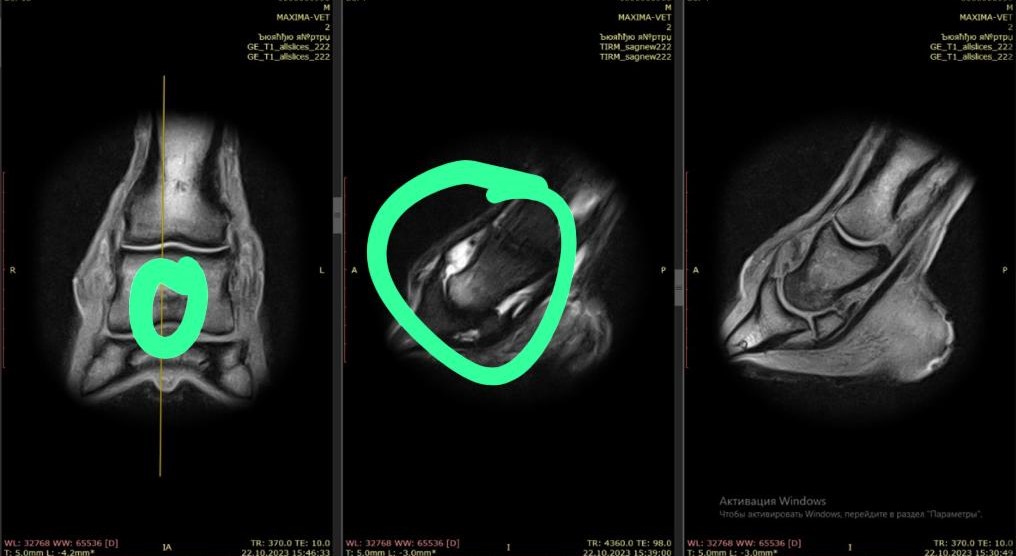

Данный пациент одним из первых попал в очередь на МРТ-обследование, имея определенную зону для обследования, постановку точного диагноза и планирования дальнейших прогнозов для спортивной карьеры.

Левая грудная конечность: переполнение и синовит копытного сустава, навикулит,

киста копытной кости.

Находки, которые определили при МРТ-исследовании, дают точный и полный

диагноз для обследуемой зоны. И самое важное – определяют возможность для

данной лошади спрогнозировать шансы возвращения в спорт, а также получить

более полную консультацию от ветеринара по консервативному и хирургическому

лечению.